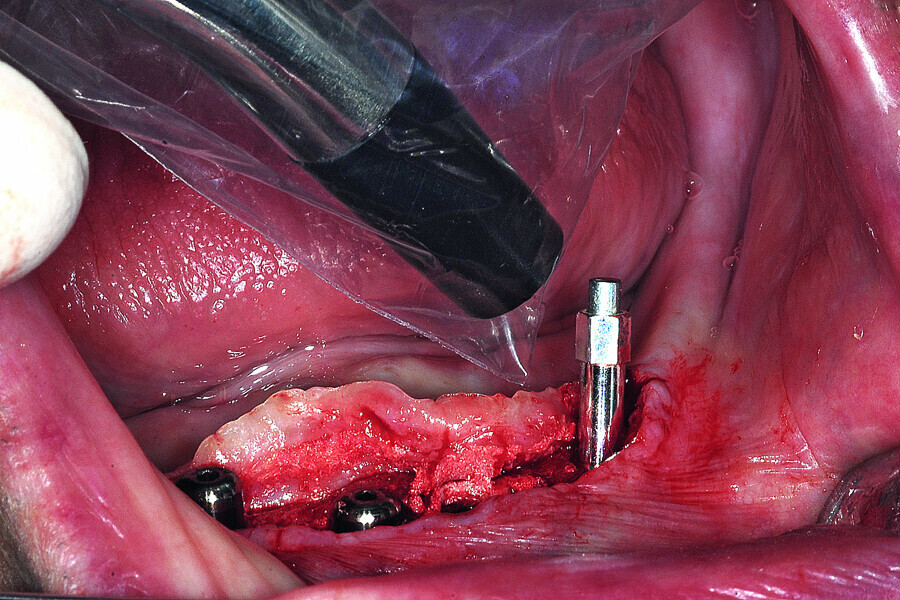

Fig. 16a: The thread design of the AnyRidge implant (a), four implants well-fixated in the mandibular symphysis (b).

Fig. 16b: The thread design of

the AnyRidge implant (a),

four implants well-fixated in the

mandibular symphysis (b).

Fig. 17: Each of the four implants was measured for implant stability with the implant specific SmartPeg.